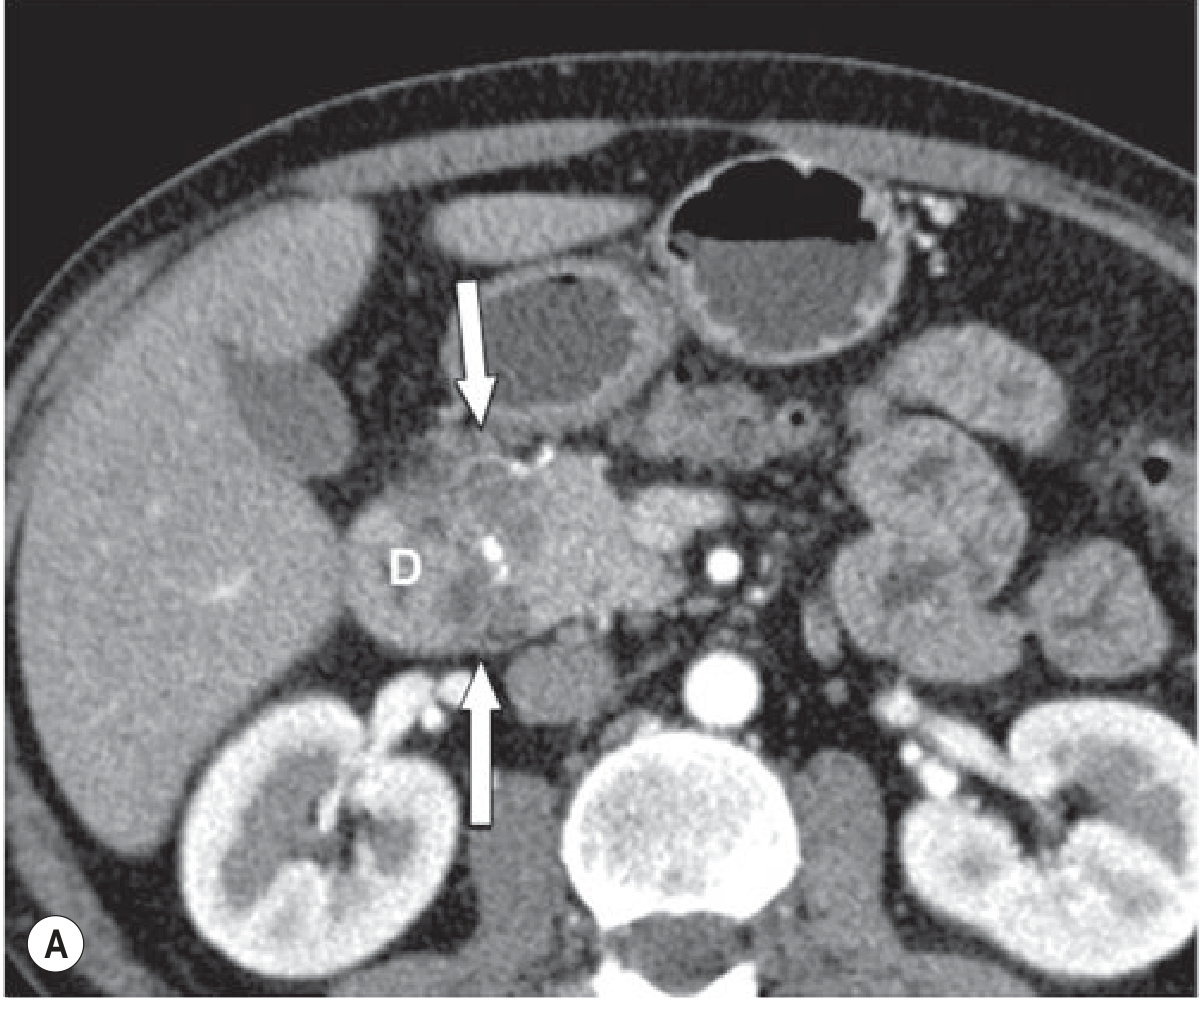

Fig. 25.23A (Grainger & Allison's) — CT showing the low-density groove mass (arrows) between the pancreatic head and duodenum (D):

CT groove-predominant paraduodenal pancreatitis — low-density mass between pancreatic head and duodenum

• Groove-predominant form: plate-like, hypoattenuating (low-density), poorly enhancing lesion situated between the pancreatic head and the descending duodenum (labeled "D" in the CT below — arrows point to the mass)

• Diffuse stranding and inflammatory changes surrounding the first portion of duodenum

• A curvilinear or cystic fluid collection in the groove — subtle but classic for groove pancreatitis

• Pancreatic and/or bile duct dilatation may be present

• The main pancreatic parenchyma is largely unaffected (groove-predominant form)